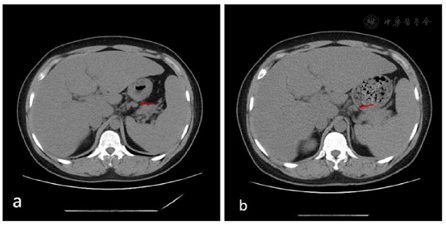

为进一步诊治,将患者收治入院。考虑到LCH多为多器官累及,完善了相关检查。甲状腺实验室检查:T3 1.33ug/L,T4 34.40 ug/L,FT3 4.46 pmol/L,FT4 5.62 pmol/L,ATG-Ab 161.2 kU/L,TPO-Ab 40.8 kU/L;24小时尿量7600 ml,尿比重(折射仪法):1.0027;颅脑MRI平扫提示鞍上池病变(鞍上池区见结节状异常信号灶,呈稍长T1稍长T2信号,边界欠清,大小约2.3 cm×1.6 cm);腹部CT示肝胃间隙、后腹膜多发淋巴结肿大。